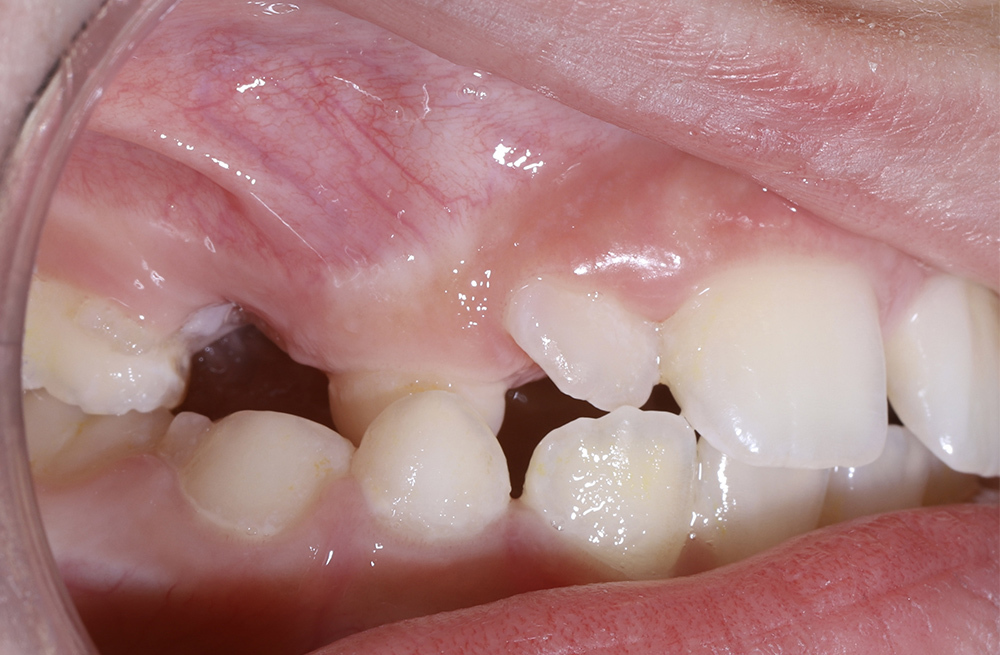

Коррекция дефицита пространства для постоянного зуба ортодонтическим методом